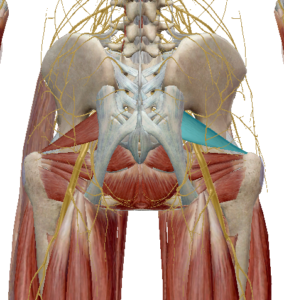

(4) 이상근

이상근은 천골의 앞쪽에서 부터 대퇴골의 위쪽을 향하고 있습니다.

고관절을 외회전 시키며 이상근 아래로 좌골신경이 지나가면서 좌골신경통의 원인으로 주목받고 있습니다.

이상근이 주목받는 또 다른 이유로는 기능의 변화입니다.

이상근은 고관절이 90도 이상 굴곡될 경우 고관절 내회전으로 기능이 변화합니다.

이는 근육의 기능은 해부학적 자세에서 기록된 것이며 자세에 따라 다르게 작용할 수 있다는 근거가 됩니다.